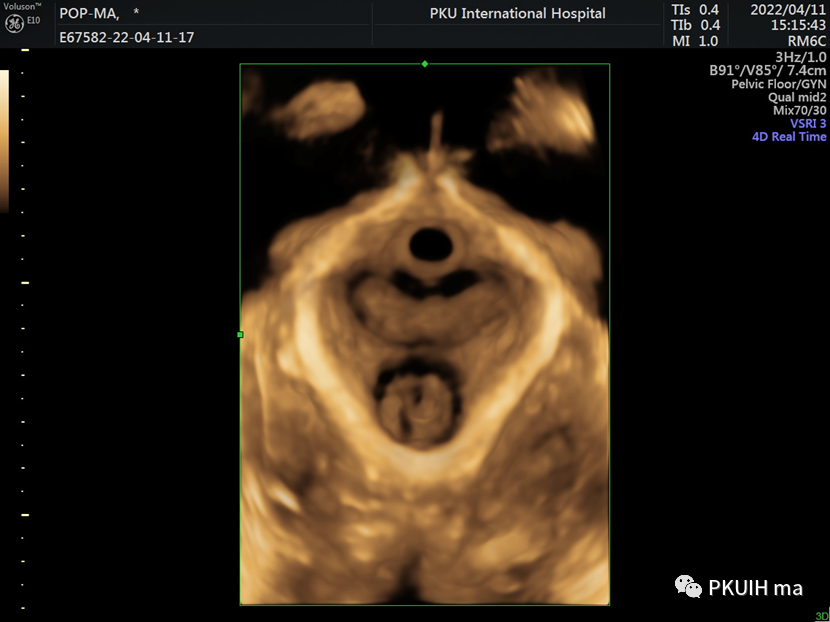

四维超声显示肛提肌裂孔面积和整个肛提肌的完整性